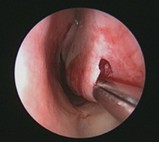

以微創鼻甲成型術縮減(右)

* 微創下鼻甲成型術:在局部麻醉下,以微創刀片伸入下鼻甲之黏膜下層並進行刮取及抽吸,使其組織減少並進而纖維化來縮減體積。

* 下鼻甲切除術:在局部或全身麻醉下,將一部份之下鼻甲骨片切除,並同時移除其上附著之部份下鼻甲黏膜,使下鼻甲的體積大幅縮減而達到較佳的鼻道通暢度和較長的術後效果維持。